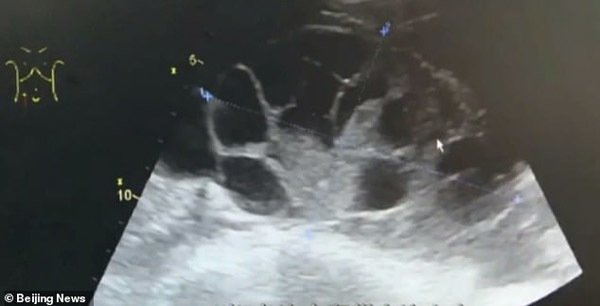

Một người phụ nữ bình thường rụng một trứng mỗi tháng nhưng nữ sinh viên Trung Quốc đã bán 29 trứng trong hai lần bán.